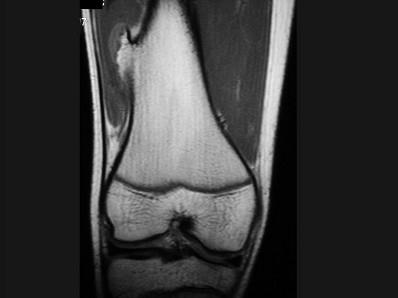

问题 男,13岁,运动后膝痛,请结合影像图像,选择最可能的诊断 ( )

选项 A、成骨细胞瘤 B、骨样骨瘤 C、动脉瘤样骨囊肿 D、骨软骨瘤 E、正常影像

答案 D